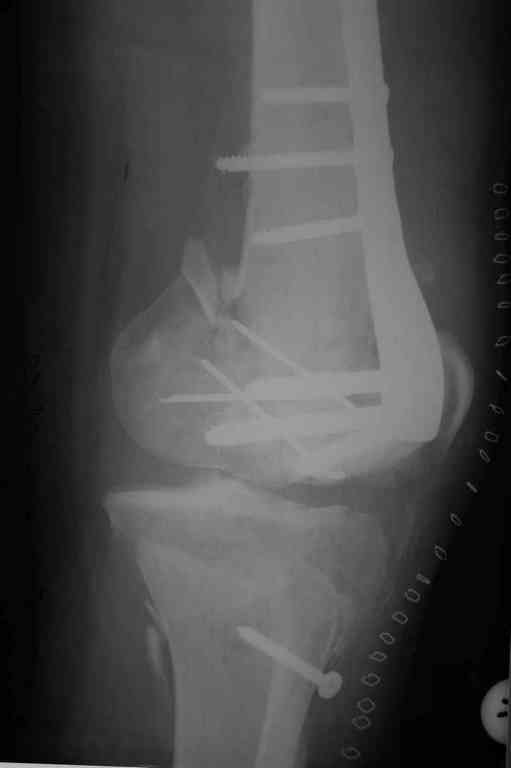

Поступила к нам пациентка 19 лет с диагнозом "Состояние после открытого многооскольчатого перелома дистального метаэпифиза правого бедра, проксимального метаэпифиза большеберцовой кости". Травма в июне 2010 года в Индии. ДТП.

Тамошние доктора выполнили ПХО с удалением фрагментов латерального мыщелка бедра. Наложен АВФ. По возвращению в Украину через 1,5 месяца АВФ демонтирован. И так как смещение фрагментов бедра не устранено, было принято решение после заживление ран от стержней выполнить МОС. Не сколько для четкой анатомической репозиции сколько для подготовки к установке эндопротеза в будущем. Что и было выполнено 10 августа. Интраоперационная картина следующая. Дефицит практически всего латерального мыщелка бедра. Была выполнена попытка закрепить то что осталось от мыщелка, но он развалился на фрагменты. ВЫполнен ситуационный синтез спицами. Дефект заполнили бикортикальным трансплантатом из крыла подвздошной кости, МОС страйкеровским фиксатором. В послеоперационном периоде к 10 дню начались боли, гипертермия. Повышение СОЭ, лейкоцитоз. Посев крови транзиторная бактериемия золотистого стаф. Взяли в операционную. Выполнили дренирование сустава и области п\о раны. Получили гематому фактически с гноем. Температура нормализовалась. Назначили ванкомицин по 1000 мг 2 раза в день.который принимает с 28 августа по сей день. Температура нормальная, СОЭ на убыль. Посевы отделяемого стафилококк 2 ст активности. Но отделяемое по дренажам продолжает идти в достаточном количестве. Взял посев, сеется стаф. 3 ст активноси. К ванкомицину, понятно, слабочувствителен. Что в этой ситуации посоветуете?

Коллеги фиксатор Numelock II

На вашем снимке из-за ротации трудно угадать положение пластины, и желательно сделать снимок с захватом верхнего участка бедра.

Одинокий кортикальный шуруп не удержит тибиальный бугор, сустав тибиал плато оставлен без репозиции и фиксации.

План с протезированием чересчур агрессивный, больная слишком молодая. В данный момент для удержания конструкции необходимо установить наружный фиксатор между бедром и голенью. Обработку продолжать с применением антибиотиков и вакуумирования.

Здесь применение материала Plexur http://www.plexur.com для пластики при дефектах кости у больной с огнестрельной раной латерального тибиал плато с повреждением малоберцового нерва. Несмотря на интактный медиальный мышелок, для профилактики от вальгуса установлен АВФ и сделана ангиограмма.

После нескольких обработок и вакуумирования, поэтапно сделана фиксация тибиального бугра шурупами. И окончательную фиксацию закончили латеральной пластиной для тибиал плато и установкой пластического материала.